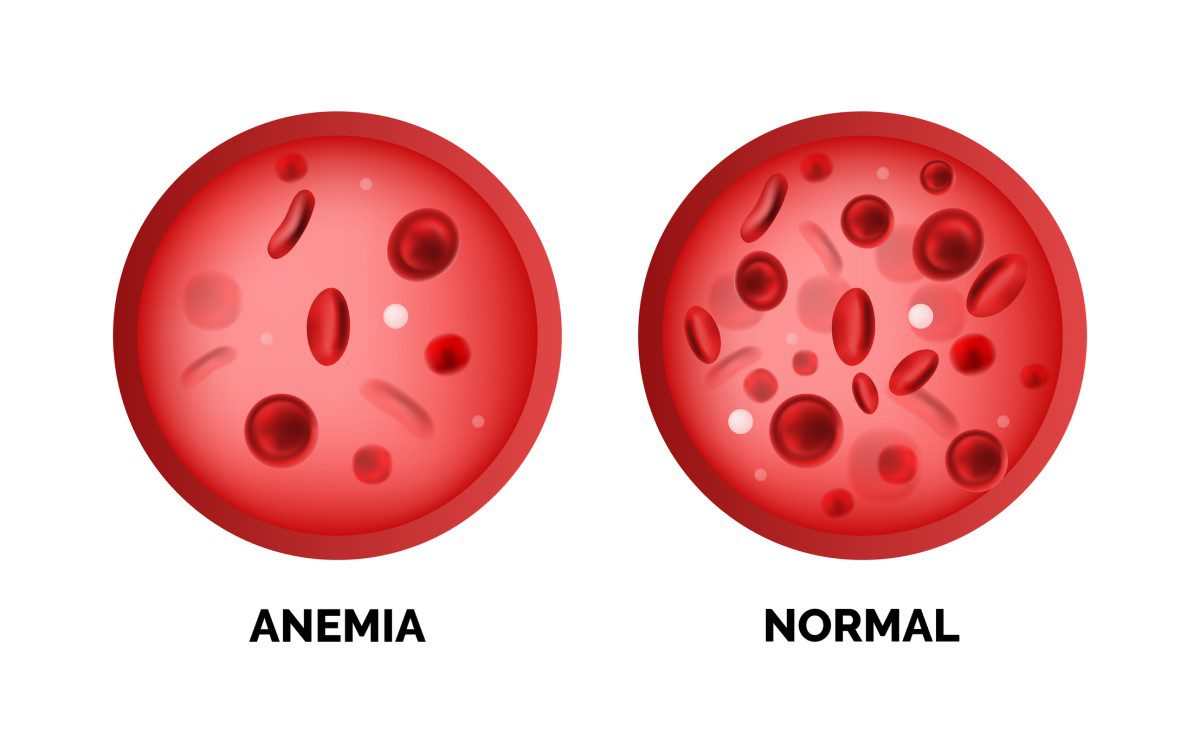

Anémia

U ľudí sa vyskytuje častejšie ako by si mnohí mysleli. Nie je to také jednoduché, no často za to môže práve nedostatok železa. Ak sa teda často cítite mdlo, máte triašku a ste neustále unavený, bez energie, navštívte svojho lekára a požiadajte ho o kompletné hematologické vyšetrenie.